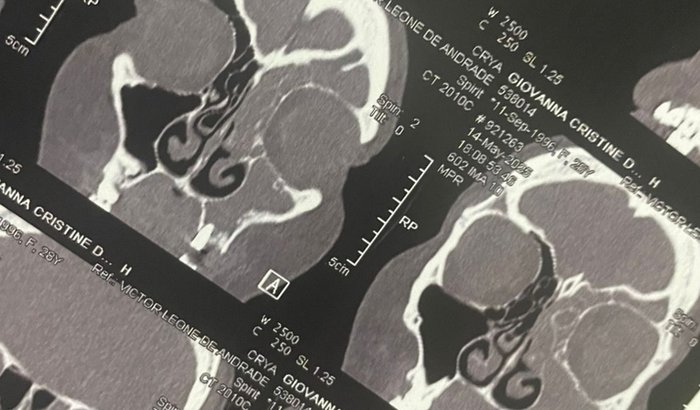

Já estou no sétimo antibiótico, fiz cirurgia (que deu errado) e vou precisar mantendo continuidade no tratamento, estou usando muito dinheiro nisso com remédios e agora consultas e exames particulares, pois não tive amparo no convênio (ao qual já sai), iniciei um protocolo com o novo convênio médico após ter problemas até com as vias particulares. Hoje 11/julho, fui ao otorrino com uma nova e atualizada tomografia em bom estado, e em resumo continuo com a secreção. O médico literalmente usou as palavras “honestamente parece que nem houve intervenção cirúrgica”. Novamente tive que tomar corticoide, e meu problema na coluna se agravou também e fui ao ortopedista, vou iniciar protocolo de fisioterapia, RPG (reconstrução postural global) e acupuntura para alívio de dores (ainda não esto autorizada a voltar para academia) Estou pedindo ajuda pra conseguir lidar com esses gastos que estou tendo e ainda vou ter, só quero que isso acabe. Sinto muita dor e sinto que nenhum médico tem me dado amparo adequado, até agora. Os medicamentos estão afetando meu organismo, não consigo enxergar direito, sinto muita dor (a ponto de internarem para controlar), a quantidade de medicamentos que já tomei me prejudicam em outros aspectos, a falta de atividade física prejudica ainda mais meu problema na coluna. Tudo virou uma bola de neve de problemas! Me encontro literalmente perdendo minha vida e tempo por causa dessas condições. Minha saúde mental está esgotada, além do físico.